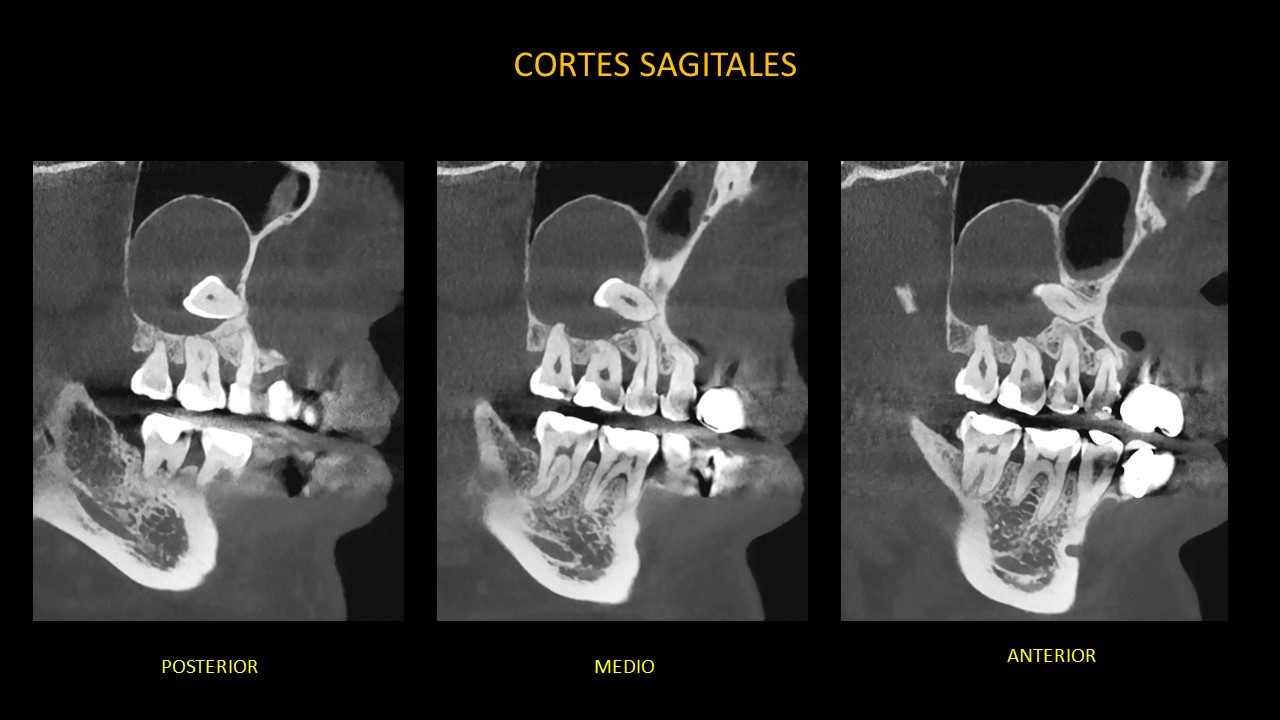

Figura 4

En la vista sagital (Figura 4), se observa la extensión de la lesión en sentido mesial-distal desde la pared lateral de la fosa nasal derecha hasta la pared posterior del seno maxilar derecho; así como la erosión parcial de la pared posterior del seno maxilar derecho.